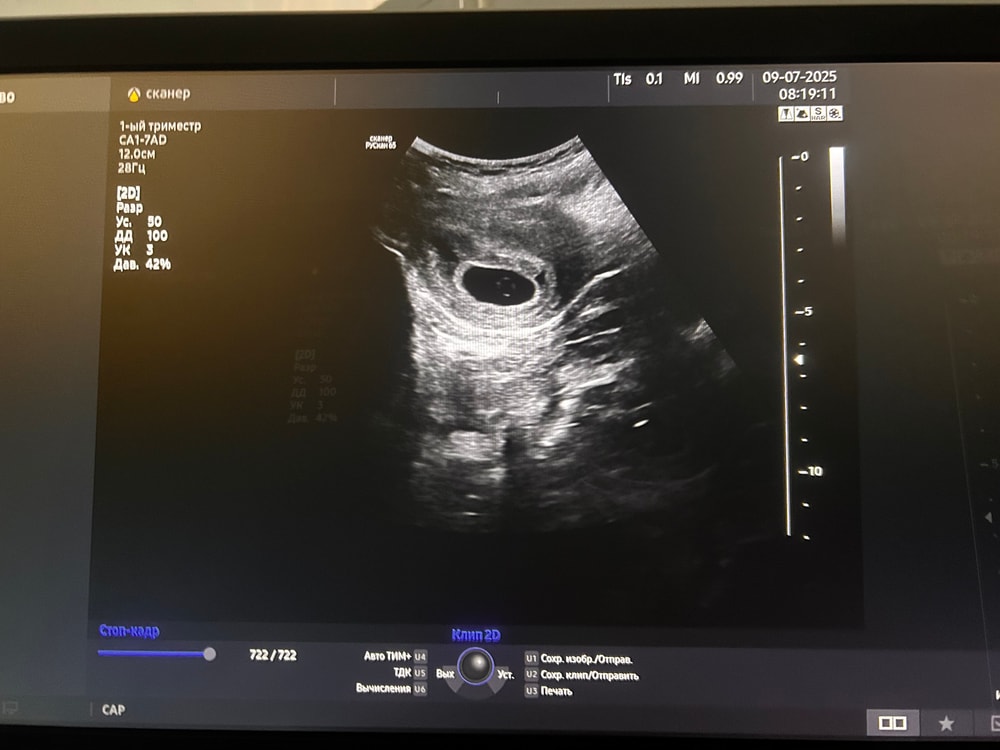

мне 20. беременность первая и соответсвенно желанная. Лежала на сохранении из-за гематомки маленькой, сегодня выписали.. Мои последние месячные были 10 мая, тесты начали полосатится 10 июня и 11 июня но полоска вторая была бледная.. цикл 31-32 дня возможно была поздняя овуляция..Делали узи по узи видно только желточный мешочек и плодное яйцо но эмбриона нет..

плодное яйцо 16мм

ктр 2,6

Ктр 2,6 - это размеры эмбриона